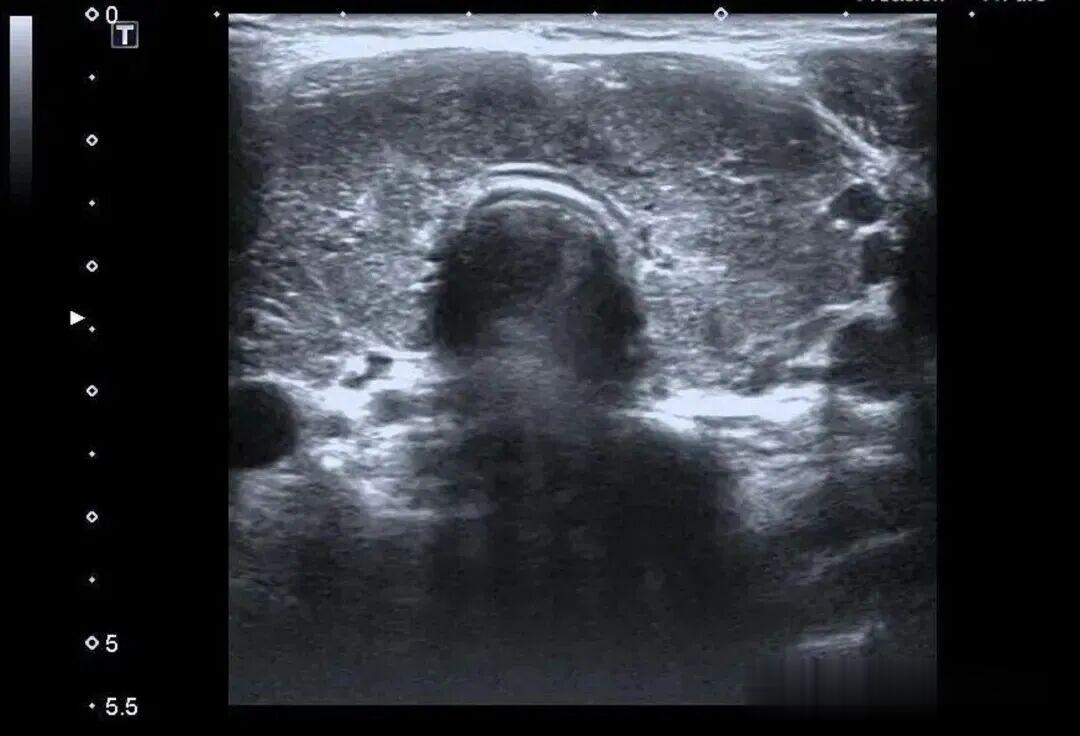

而更致命的隐患藏在她的病史里——陈女士是一位有着20年甲亢病史的患者,并且已经自行停药一年。鉴于病情危重,陈女士被紧急转入瑞金医院卢湾分院内分泌科。

甲状腺功能检查中,游离T3高达20.83pmol/L(正常值3.5-6.5pmol/L),游离T4高达88.42pmol/L(正常值11.5-22.7pmol/L),这两项核心激素都超过正常上限数倍,而本应调控它们的促甲状腺激素(TSH)却几乎测不出来,这明确证实了陈女士患有极其严重的甲状腺毒症。心脏超声结果同样不容乐观,射血分数仅有40%(正常应高于55%),这意味着心脏泵血能力大幅下降。

同时,CT检查发现她的双侧胸腔、腹腔存在积液。综合各项检查结果,医生判断陈女士患上了甲状腺危象,这是甲亢最凶险的并发症。